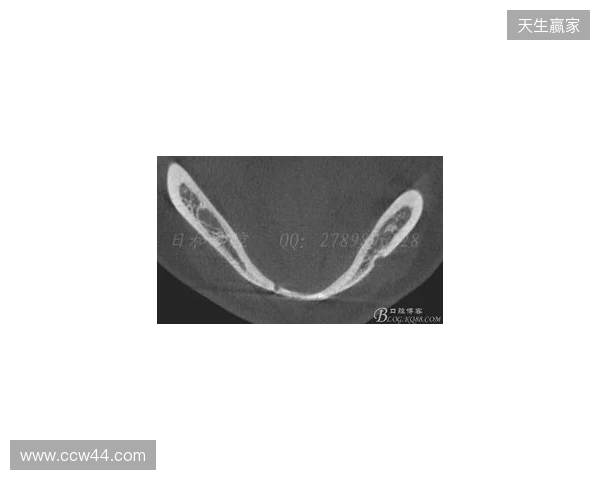

在2026赛季中超联赛首轮的比赛中,韦林顿·席尔瓦遭遇了严zoty中欧重的伤病,导致他上唇部受伤,并且出现了牙齿和牙槽骨的损伤。根据华西口腔医院的诊断,席尔瓦的伤情包括上唇部贯通伤、两颗牙齿半脱位以及上颌前牙区牙槽骨骨折。此事件不仅对球员本人构成了巨大的身体挑战,也给球队带来了不小的影响。伤病的发生让人揪心,球迷们纷纷为席尔瓦送上祝福,希望他能尽快康复,重返赛场。

根据医院的检查结果,韦林顿·席尔瓦的上唇部受伤程度较为严重,属于贯通伤,已经进行了清创缝合。这种类型的伤势不仅影响外观,还可能对球员的饮食和发声造成影响。更为严重的是,他的上颌前牙区还出现了骨折,意味着席尔瓦在恢复期间将面临长时间的治疗和康复过程。

球员的第11和第21牙出现了半脱位的情况,这可能会导致他在恢复后需要进行进一步的牙科治疗,甚至有可能影响到他今后的职业生涯。医生表示,虽然通过手术和治疗可以恢复,但心理层面的恢复同样重要。